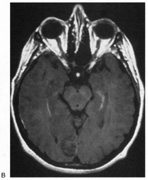

Fig. 5. Macula-splitting hemianopia. A 47-year-old man with AIDS and sudden onset of poor vision. A. Fields show complete left hemianopia. B. MRI shows lesion of right lateral occipital cortex, affecting distal optic radiations. Biopsy showed nonspecific encephalitis.

Fig. 6. Lesion of temporal optic radiation. Left superior quadrantanopia, respecting horizontal meridian (A), from infarct of right medial temporal lobe, in posterior cerebral artery territory (B). (From Rosen ES, Eustace P, Thompson HS, Cumming WJK [eds]: Neuro-Ophthalmology. London: Mosby, 1998.)